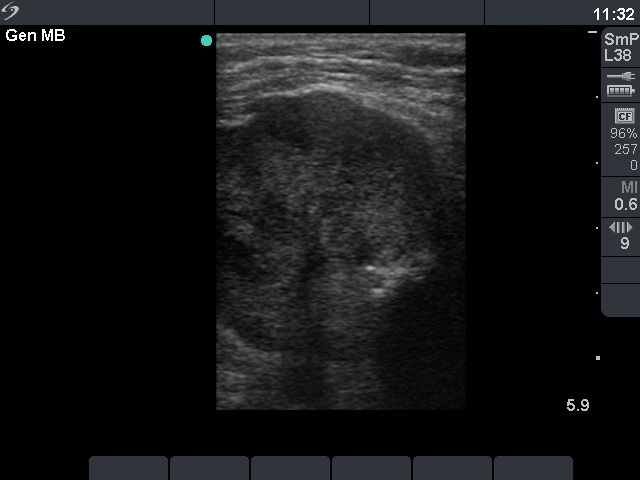

Tall cell variant of papillary carcinoma (ultrasonographic picture 3)

Left lobe, longitudinal view. The nodule contained coarse and microcalcifications. Note that the depth had to reset to 59 mm in order to visualize the dorsal part of the nodule.